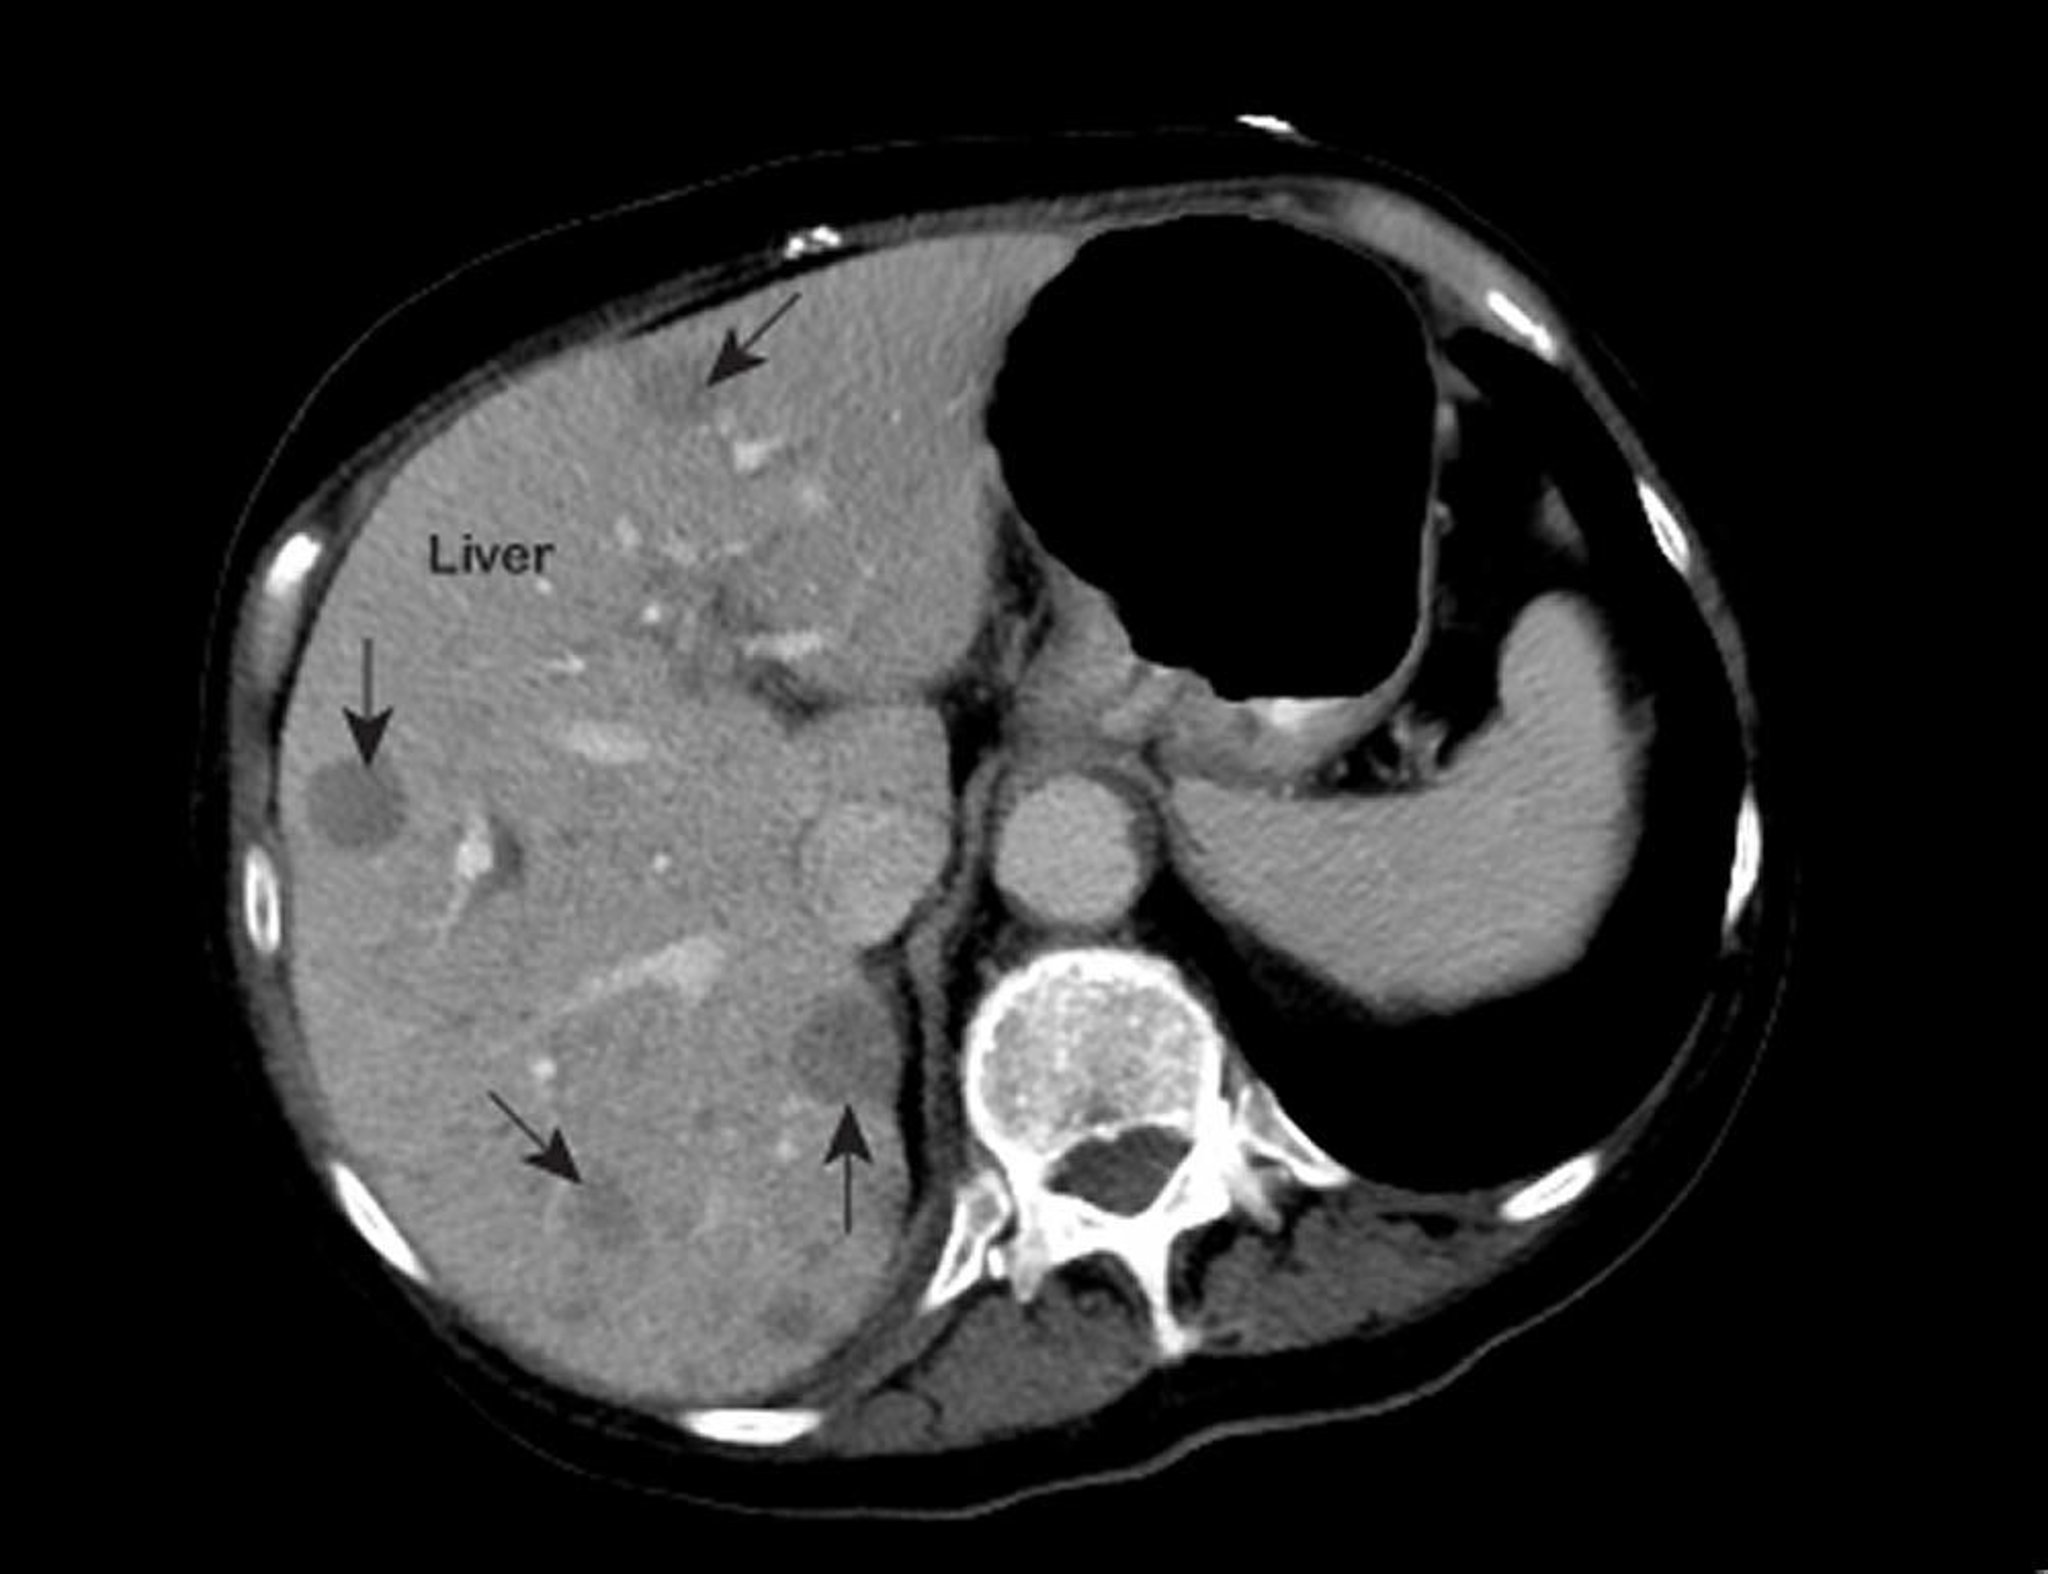

Метастатический рак печени

На изображении, полученном с помощью магнитно-резонансной томографии (МРТ) органов грудной клетки, показаны аномальные участки в печени (обозначены стрелками). Эти результаты типичны для метастатического рака печени.

Фотография любезно предоставлена д-ром Патриком О'Кэйном [Patrick O’Kane, MD].